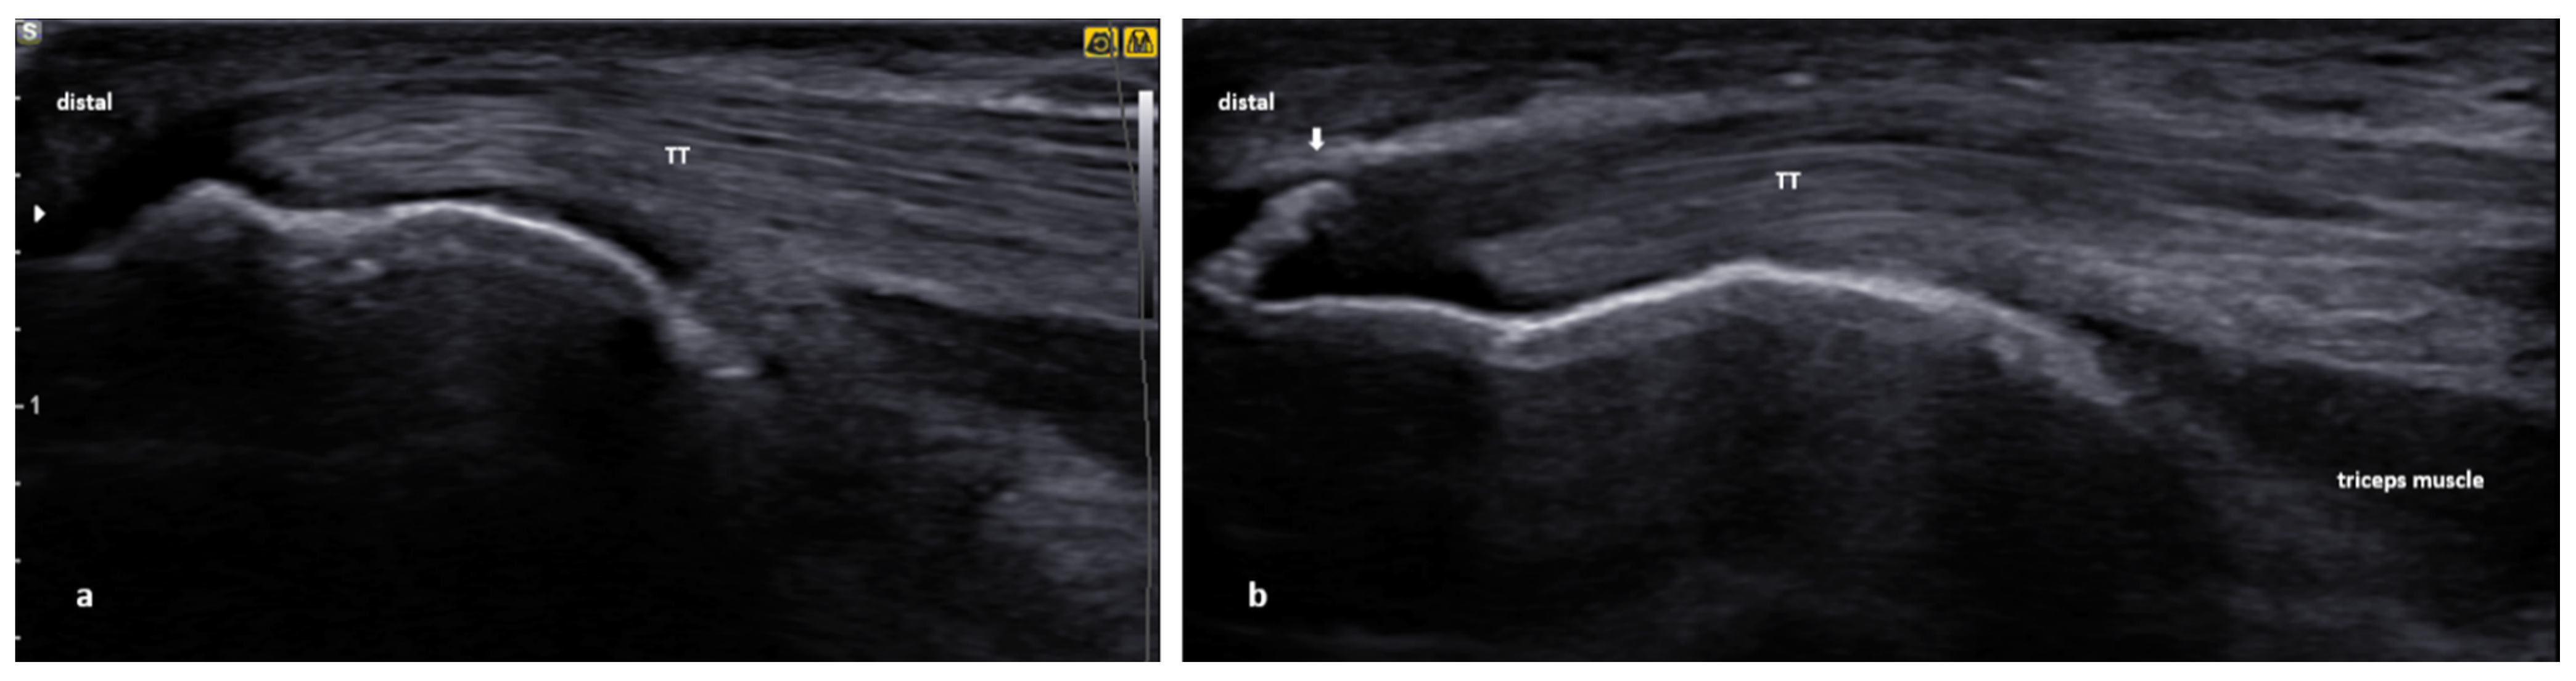

The triceps tendon (TT) evaluation can be performed with the patient positioned semi-supine on the examination bed. Using this positioning technique, the elbow rests on the patient’s stomach, while the elbow is free for flexion/extension dynamic assessment. The dynamic evaluation is useful to assess for the TT continuity but also to rule out the presence of fluid/loose bodies in the olecranon fossa. For the TT assessment—the longitudinal view—the examiner can see the myotendinous junction and the TT insertion footprint on the olecranon (Figure 12a). The US features of TT tendinopathy comprise local hypoechogenicity, tendon thickening, hypervascularity, calcifications, and bony irregularities/spur (Figure 12b). Triceps tendon tendinopathy is rare; however, inflammation of the overlaying olecranon bursa is more common, particularly following trauma or in patients with inflammatory diseases. The way to aspirate olecranon bursitis should be decided with respect to local anatomy (e.g., septa, adjacent structures). Notably, US guidance provides clinicians freedom in all interventional procedures [88]. There is little evidence using US-guided injections in triceps tendinopathy. Cheatham et al. [89] reported a case report of a patient with distal triceps partial tear treated with PRP injection and rehabilitation, resulting in pain-free activities of daily living and return to preinjury sports activity after four months. When injecting TT, a potentially vulnerable structure would be the ulnar nerve, which passes medially along the tendon. Using the lateral approach and the US guidance can reduce the risk of iatrogenic injury to the nerve (Figure 13).

Figure 12.

Ultrasound images of the distal triceps tendon (TT): (a) normal longitudinal image of the TT; (b) US image that demonstrates a prominent spur (white arrow) at the olecranon’s TT insertion site.